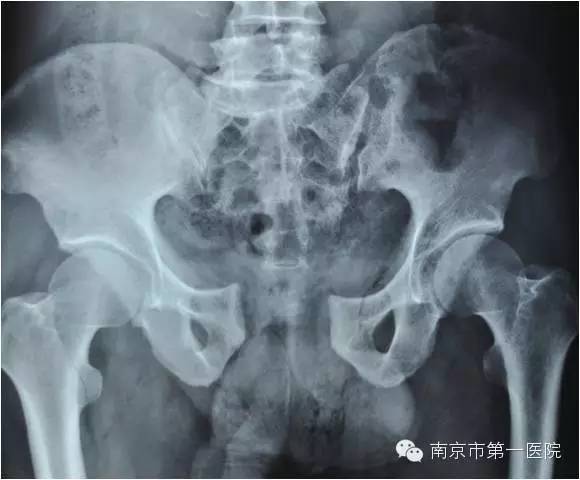

随后,老张第一时间被送到当地医院进行了简单处理,处理完又立刻转到南京市第一医院进行进一步抢救。据了解,小卡车大约1.5吨重,受伤的部位在骨盆,因为受到碾压和挤压,导致骨盆内的肌肉撕裂、血管损伤,骨盆也粉碎性骨折。另外,同时存在右侧胫腓骨粉碎性骨折及大面积软组织损伤。

据了解,骨盆骨折是一种严重外伤,占骨折总数的1%~3%,多由高能外伤所致,半数以上伴有合并症或多发伤,致残率高达50%~60%。因此,在对患者进行输血、补液、液体服务等抗休克治疗的基础上,ICU立即组织院内骨科专家进行会诊。